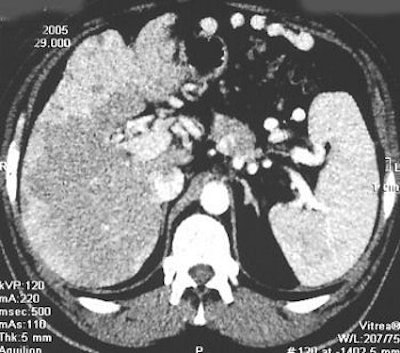

![]() |

| Search for primary tumor after detection of bilateral ovarian metastases of well-differentiated endocrine tumor. Bilateral ovariectomy was performed as part of radical surgery for uterine carcinoma. CT and contrast-enhanced bowel x-rays were negative. Primary tumor was clearly identified with 18F-FDOPA PET/CT. Copyright © 2006 by the Society of Nuclear Medicine. |